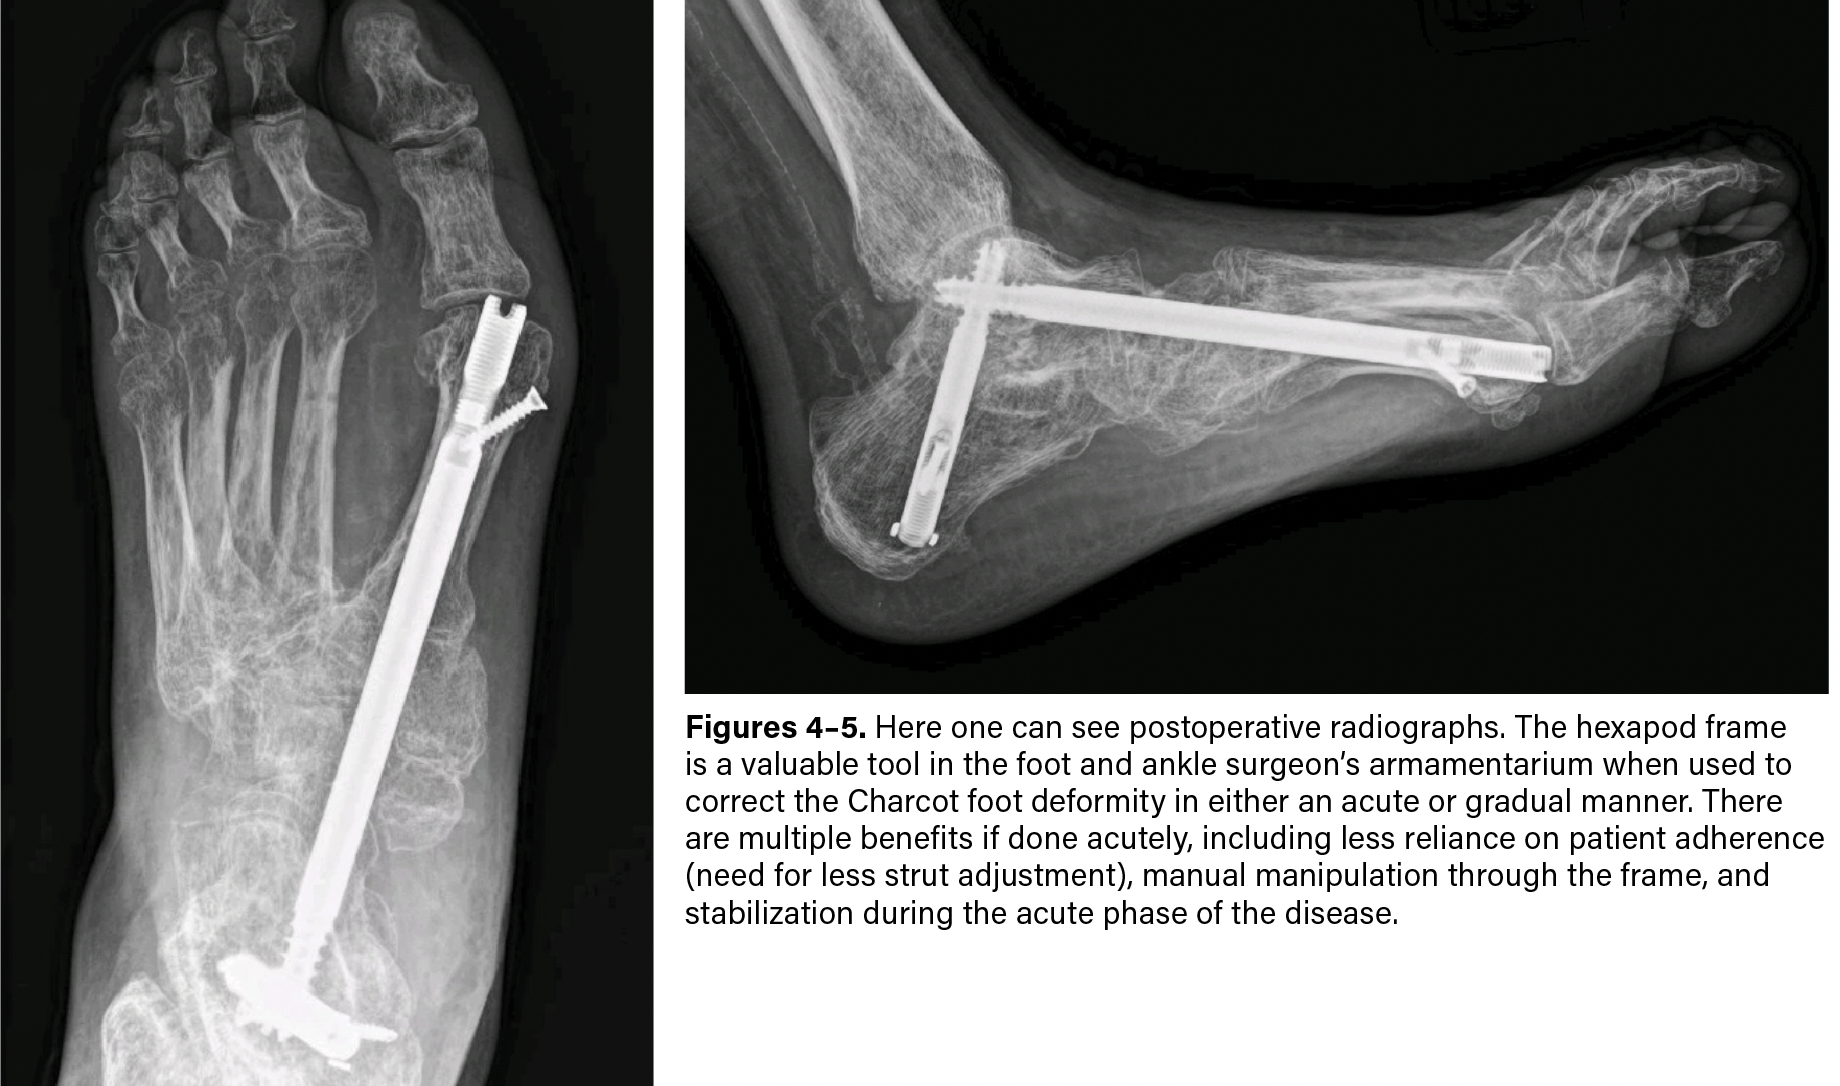

Stage 2: Transition to internal fixation. In Charcot patients undergoing staged reconstruction with an application of internal fixation, we have employed a minimally invasive approach to our joint preparation due to their increased risk for nonhealing wounds, necrosis, and infection (if not already present). Using fluoroscopy as a vital tool with this approach, we utilize the mini-C arm for accessibility and maneuverability. Position the bed so there is ample room for the C-arm to move with ease.

It is also essential to have an excellent understanding of the anatomy of the area one is fusing, as you will need to maneuver the burr around the contours of bone to ensure appropriate joint preparation as well as to avoid critical vascular structures. Using the medial column as an example, we mark out the location of each joint (first tarsometatarsal joint, medial cuneiform-navicular, and talonavicular) both on the dorsal and medial aspects of the foot using the AP and lateral projections. Then make a stab incision centrally over each joint and carry blunt dissection down to the bone. We then introduce a percutaneous burr to remove cartilage and subchondral bone. This can be under live fluoroscopy, but if the surgeon is comfortable with utilizing the percutaneous burr, then one can use fluoroscopy more sparingly to ensure adequate joint preparation. Be sure to “milk” each incision to remove the bony-cartilaginous debris. Intramedullary beams and bolts have served us well and allow for a limited skin incision approach.

Regardless of the technique, the hexapod frame is a valuable tool in the foot and ankle surgeon’s armamentarium when used to correct the Charcot foot deformity in either an acute or gradual manner. There are multiple benefits if done acutely, less reliance on patient adherence (need for less strut adjustment), manual manipulation through the frame, and stabilization during the acute phase of the disease.